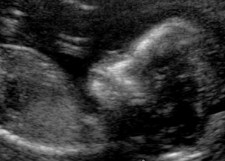

But this was probably not the first thing that came to mind when realising we were going to have our own – dazed shock at the unlikelihood of it was closer to the reality.

Four or so months later it’s still surreal but a gift – of the change-your life forever nature.